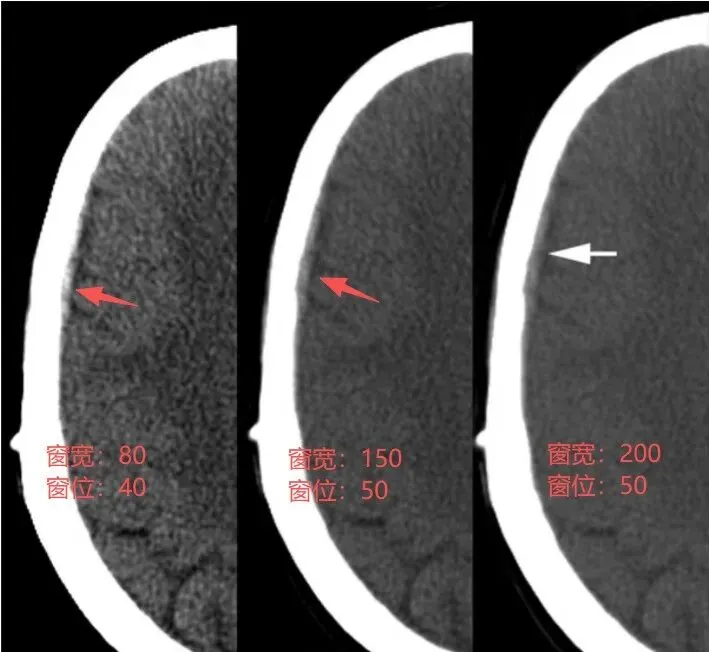

案例1:增大窗宽的案例

第一种情况是:有低密度的脑组织,较高密度的出血,高密度的颅骨,三者都要显示,就要调高窗宽,才能显示这么多结构。